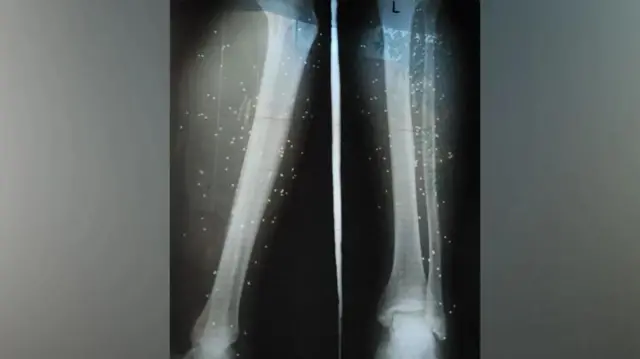

Alisema daktari bingwa wa upasuaji baadaye aliweza kuondoa baadhi ya risasi za ndege nyumbani lakini akawaonya: "Haziwezi kuondolewa zote na zitabaki kwenye miili yenu."

Nima pia alisema vijana wengi waliotibiwa katika hospitali yake walipata majeraha ya risasi kwenye viungo na miguu yao ambayo yalihitaji kukatwa viungo na kuwaacha na ulemavu wa kudumu.

Chanzo cha picha, Vahid Online